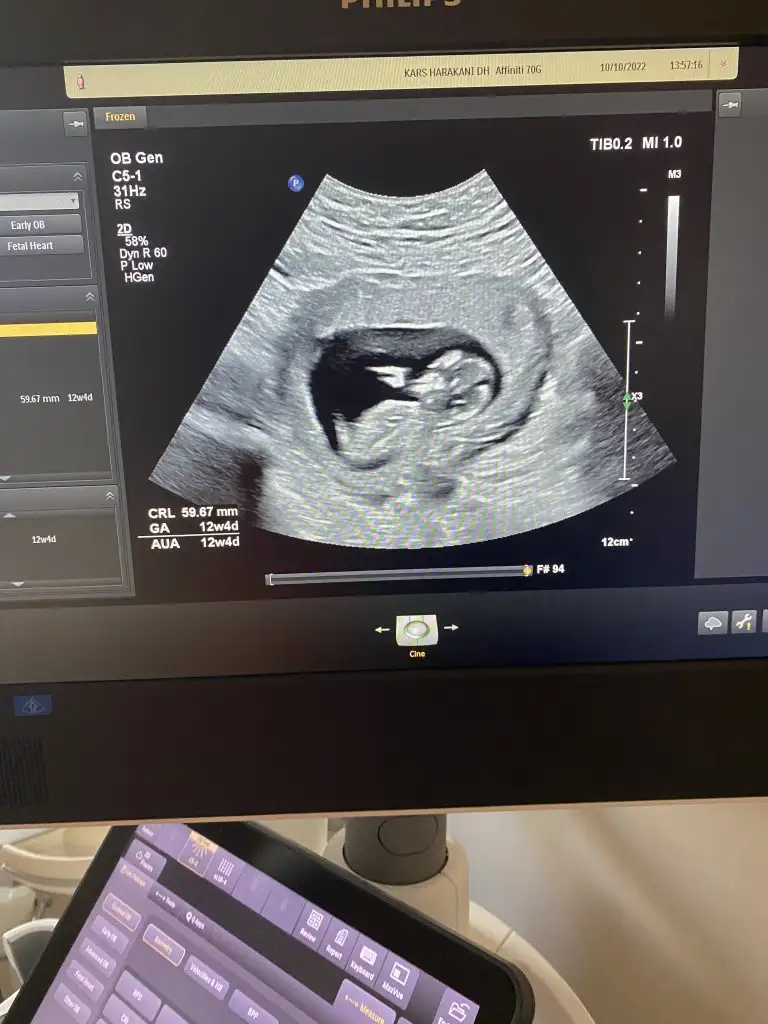

dr soylemeden siz gorun genital nub teorisi ( bebegin cinsiyeti)

Tahmininiz nedir

12 haftalık tahminde bulunabilir misiniz